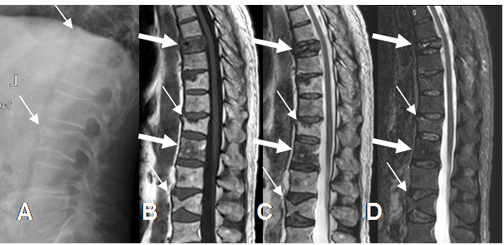

Fig 221. Fracturas benignas y malignas.

A: Rx lateral. Pérdida de altura en los cuerpos de D12 y L3.

B: RM sagital en T1, C: RM sagital en T2 y D: RM sagital en STIR. Fracturas de apariencia benigna en vértebras, con bordes angulados y preservación de la señal. (Flechas delgadas). Los cuerpos de D8 y L1 son hipointensos en T1 y T2, secundario a metástasis de tumor pulmonar. (Flechas gruesas). D8 es algo hiperintenso en STIR y tiene borde posterior convexo, en contacto con el saco dural.